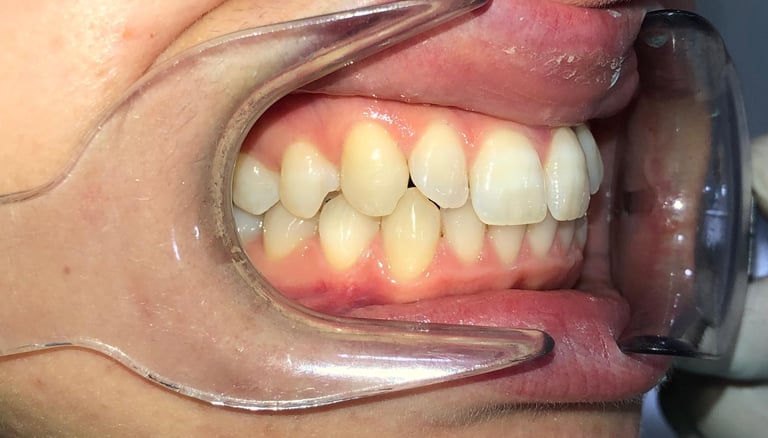

NUESTROS CASOS REALES